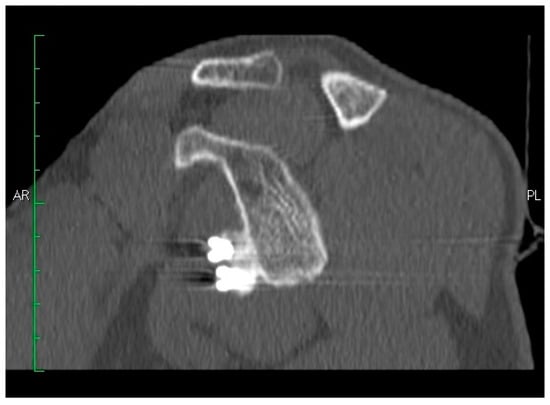

- The pectoralis minor was released, and a fresh portal was established with a needle over the coracoid, to insert the drill holes, at the junction of the lateral 2/3 and the medial 1/3. Two Kirschner wires through the coracoid were passed. The drill guide was removed. The holes were tapped, and the top hats were inserted into the fragment using a flexible Chia wire. The osteotomy was completed (Figure 2). The bone fragment was secured thought a coracoid screw passed over the Chia wire, using a double cannula.

- The graft was positioned on the anterior glenoid neck with the switching stick through the posterior portal (Figure 3).

- The graft was fixed. Two holes were made through the coracoid and the glenoid using the double cannula. Graft trimming was performed with the burr (Figure 4).